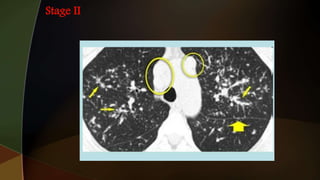

1. hilar adenopathy alone

2. hilar adenopathy plus infiltrates;

3. infiltrates alone;

4. fibrosis

Garland triad, also known as the 1-2-3 sign or Pawnbrokers sign

 Common findings: